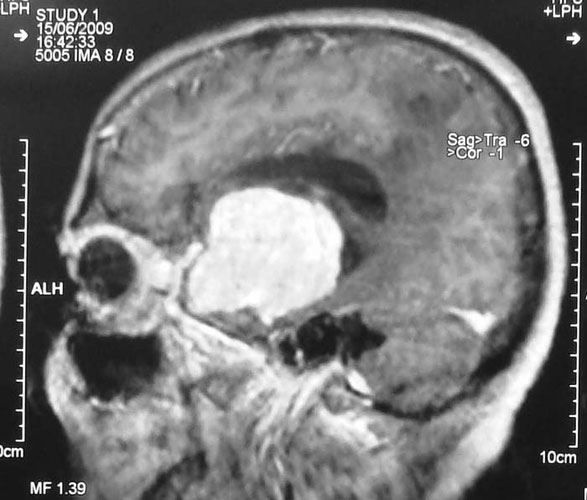

Craniopharyngioma

Craniopharyngioma is a common tumor in childhood, but can also be seen in adults. These tumors often present with endocrine problems, abnormalities of appetite, visual problems. MRI gives diagnosis and treatment involves surgery. Attempt must be made at complete excision, with safeguarding of vital hypothalamic functions. Radiation may be required after surgery to halt tumor followed by surgical excision, with excellent results.

Click here to know more about Craniopharyngioma